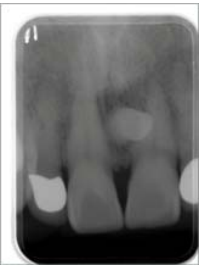

74.下圖白色箭頭所指之X光影像,下列何種病變最有可能?

(A)Squamous cell carcinoma (B)Cementifying fibroma (C)Buccal bifurcation cyst (D)Dentigerous cyst